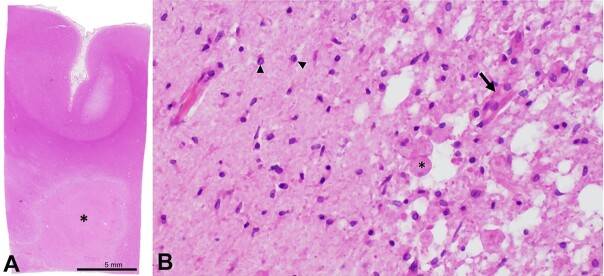

内分水岭梗死(IWIs)发生在大脑深动脉和浅动脉分支的交界处。尽管在放射学文献中有记录,但在尸检时很少遇到IWIs。在这里,我们报告一个59岁的被监禁的男性,他被发现在他的监狱牢房的地板上没有反应后被带到急诊室。初步检查和影像学表现分别为右侧偏瘫、失语、右侧面部下垂和左侧大脑中动脉严重狭窄。入院后4天和死亡前26天的重复成像显示,右侧颈内动脉交通段颅内严重狭窄,右侧大脑后动脉区域出现大面积急性梗死,双侧深部白质缺血性改变,右侧呈“玫瑰状”损伤,这是典型的IWIs。死后大体检查显示右侧深部白质病变已发展为融合性“雪茄状”亚急性IWI,累及右侧辐射冠。这是第一例有充分文献证明的IWI病例,影像学和大体病理相关联。本病例独特地突出了尸检时罕见的病变,并提供了内部分水岭神经解剖学的良好视觉表现。

Internal watershed infarcts (IWIs) occur at the junction of the deep and superficial perforating arterial branches of the cerebrum. Despite documentation in the radiology literature, IWIs are rarely encountered at the time of autopsy. Here, we report the case of a 59-year-old incarcerated male who was brought to the emergency department after being found unresponsive on the floor of his jail cell. Initial examination and imaging demonstrated right-sided hemiplegia, aphasia, right facial droop, and severe stenosis of the left middle cerebral artery, respectively. Repeat imaging 4 days after admission and 26 days before death demonstrated advanced stenosis of the intracranial, communicating segment of the right internal carotid artery, a large acute infarct in the right posterior cerebral artery territory, and bilateral deep white matter ischemic changes with a right-sided "rosary-like" pattern of injury that is typical of IWIs. Postmortem gross examination showed that the right deep white matter lesion had progressed to a confluent, "cigar-shaped" subacute IWI involving the right corona radiata. This is the first well-documented case of an IWI with radiologic imaging and photographic gross pathology correlation. This case uniquely highlights a rarely encountered lesion at the time of autopsy and provides an excellent visual representation of internal watershed neuroanatomy.